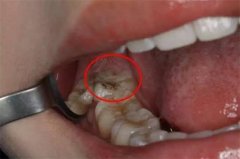

智齿蛀牙:如果智齿出现了蛀牙的情况的话,处理死死咬合面不深的简单蛀牙可以进行修补外,但是如果龋坏的牙齿有侵犯邻牙或者是龋坏严重的时候,建议将其拔除智齿是一个比较容易发生蛀牙的部位,主要是其位置比较靠近里面,我们平时刷牙很难清洁到的缘故,所以容易产生蛀牙。此类智齿需要及时拔除。

智齿是怎么拔的图解: